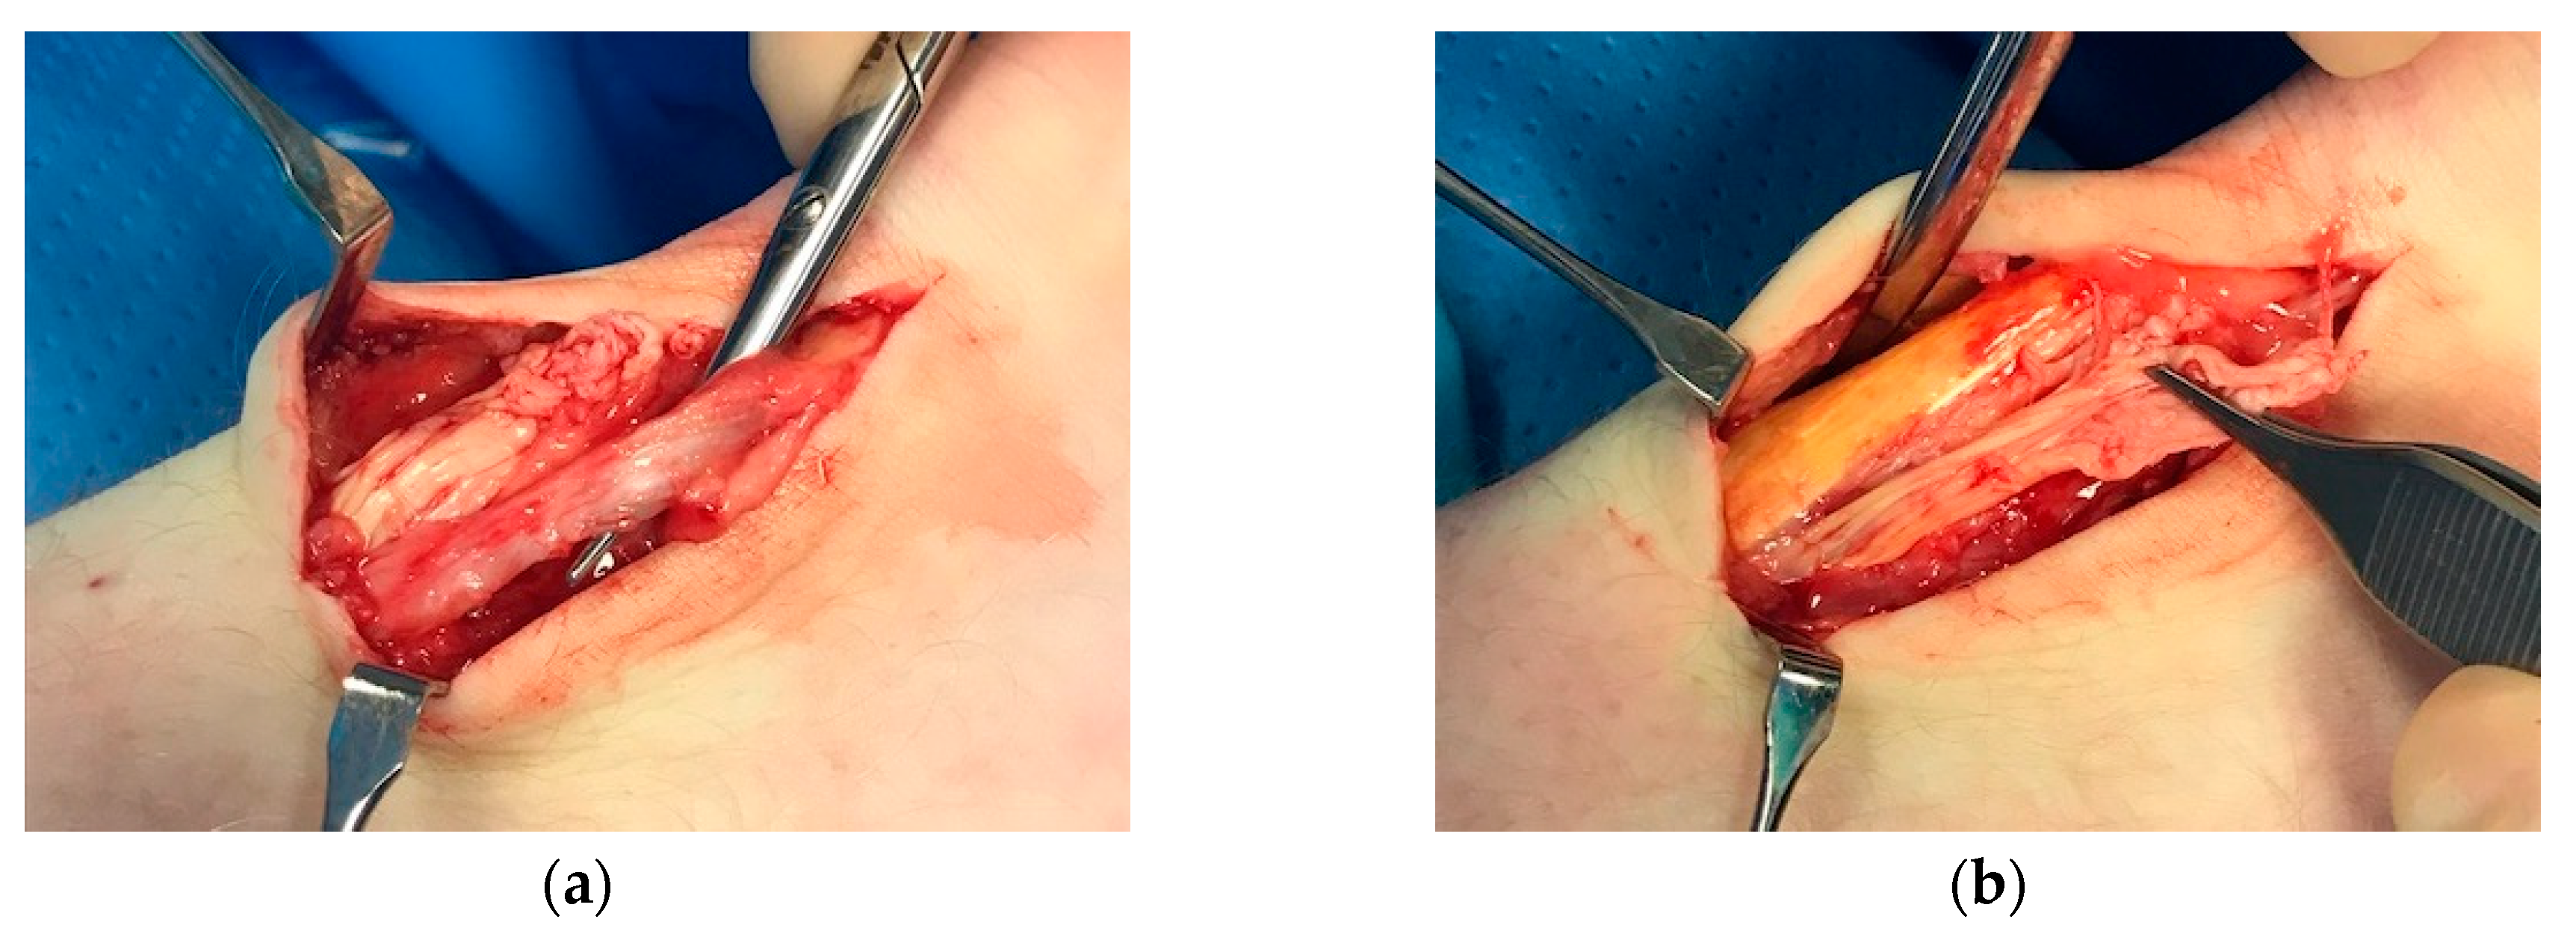

Another clinical observation from our patients is that the plantaris tendon may mimic pain from a partial Achilles tendon rupture. Typically, there is sudden sharp pain on the medial side of the Achilles, not seldom in the proximal or midportion Achilles tendon region (Figure 4). However, for plantaris-tendon-related pain the symptoms most often subside within a couple of days and then return during explosive plantar and dorsiflexion activities. Plantaris tendon involvement can be diagnosed using ultrasound [33,34,35].

Figure 4. Patient with a partial rupture in close relation to a thick and compressing plantaris tendon: (a) thickened plantaris tendon compressing onto the medial side of the Achilles; (b) surgical release of the compressing plantaris tendon.